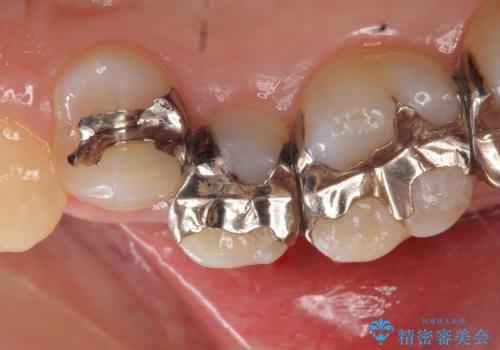

- 頬側から見たとき右上5番目の銀歯が気になるので、オールセラミッククラウンによる補綴を行った症例です。

今回用いたオールセラミッククラウンはジルコニアフレームという白い素材の上にセラミックを盛っているため、審美性が非常に高いのが特徴です。

また、ジルコニアは人工ダイヤモンドの材料にも使われているほど高い強度を持っており、そのためオールセラミッククラウンは審美性だけでなく、奥歯やブリッジの補綴も可能とするクラウンです。